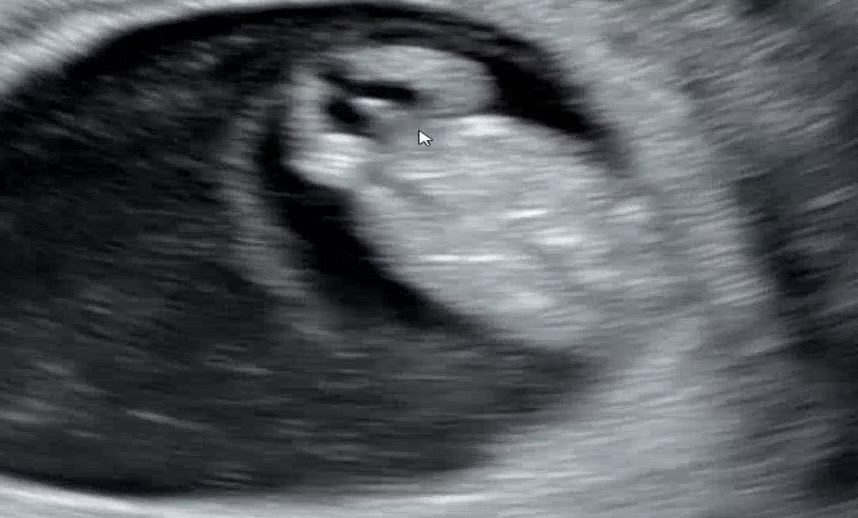

아 9주찬데 존재감이 확실하네요

둘째맘입니다. 첫째 아들 넘예쁘게 잘 키우고 있는데 체력이 넘 딸려요ㅠㅠ 둘째는 꼭 딸이길 바라는데 오늘 9주차 초음파에서 의사쌤이 아들같다고.. 하시는데ㅜㅜㅜㅜ 반전혹시 없을까요 딸에서 아들로 반전은 많던대 아들에서 딸이..별로없는거같기도하고ㅠㅠ 초음파사진한번 봐주세요ㅠㅠ 9주에 이렇게 잘보이면 아들인가요…

9주차가 맞나요?? 이렇게 잘보일수가 있나요??!!

그러니까요ㅠㅠ 저도 넘 당황..딸이기엔 존재감이 큰거같..죠..??